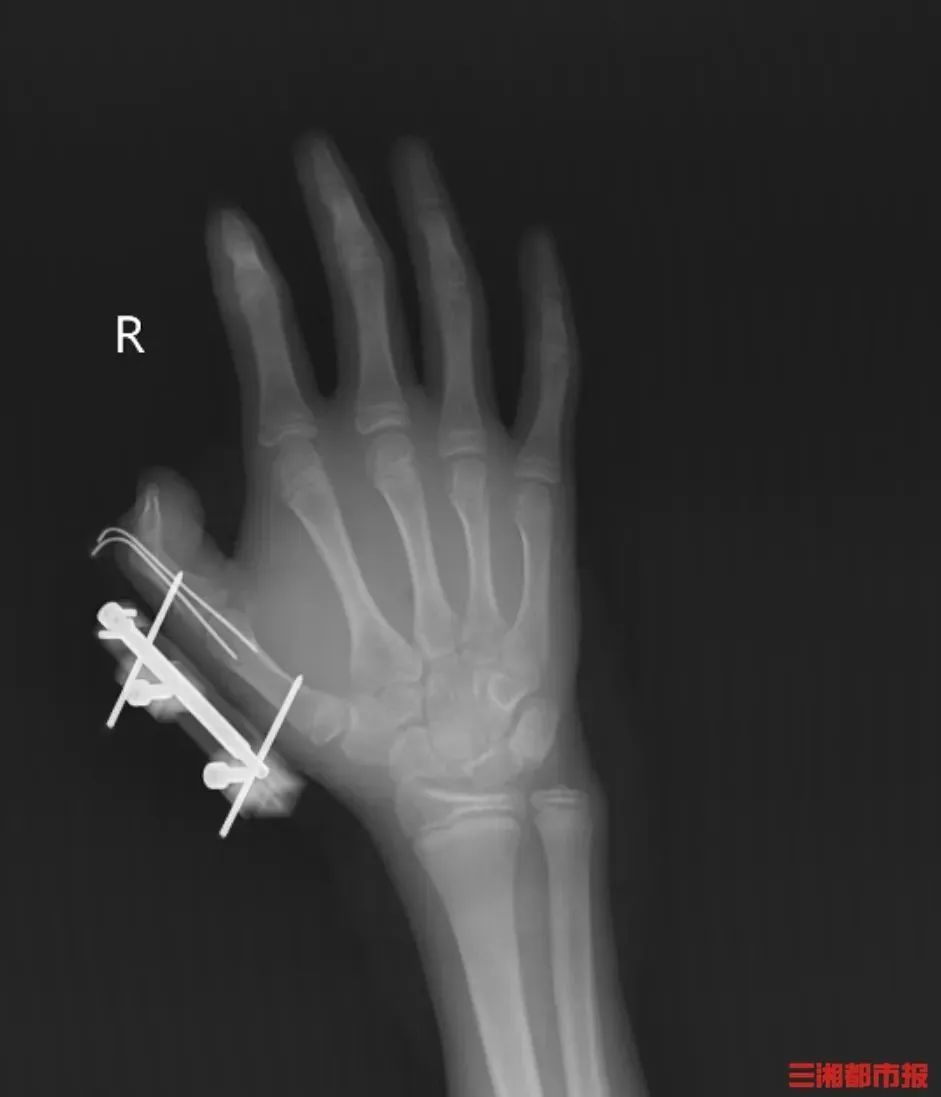

突然,密封袋里的干冰发生爆炸,维维的右手瞬间鲜血直流,拇指虎口处被撕开一道约10厘米的伤口,深可见骨,肌肉组织断裂外露,还伴随着拇指骨折、关节脱位,整个拇指完全失去知觉。

见状,家人赶紧带他到当地医院包扎,随后紧急转往湖南省人民医院手足显微外科。经治疗,维维的拇指保住了,但后续还需长期康复训练,才能慢慢恢复手部精细动作功能。维维懊悔不已:“早知道干冰这么危险,我绝对不会去玩。”